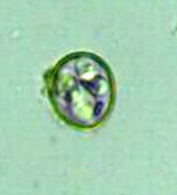

シスト、オーシストの感染があると、終宿主である猫では原虫の増殖から腸管粘膜に病変を生じますが、それは激しくなく、症状もほとんどみられない。

トキソプラズマ感染のほとんどはシスト、オーシストの経口摂取によって成立しますが、トキソプラズマ罹患動物との接触による感染も否定しえない。

オーシストは前述のように抵抗力が強いが、胞子形成以前のオーシストには感染力がないことから、猫の排泄物はすぐに処理することも予防のため必要です。